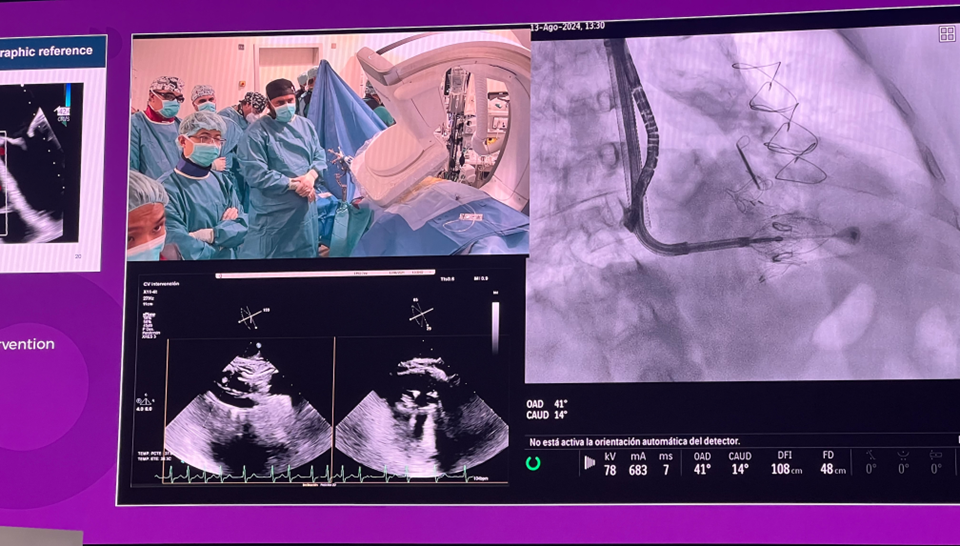

隨后由來(lái)自西班牙維哥-阿爾瓦羅昆奎羅醫(yī)院(Hospital Álvaro Cunqueiro, Vigo, Spain)的 Rodrigo Estevez-Loureiro 教授在大會(huì)主會(huì)場(chǎng)的經(jīng)導(dǎo)管介入瓣膜新技術(shù)環(huán)節(jié),帶來(lái)了一例 LuX-Valve Plus 手術(shù)錄播,對(duì)手術(shù)植入的步驟和關(guān)鍵要點(diǎn)進(jìn)行了詳細(xì)深入的介紹。同時(shí),臺(tái)上的多位討論嘉賓也結(jié)合他們的 LuX-Valve Plus 手術(shù)經(jīng)驗(yàn)進(jìn)行了深入的探討。來(lái)自香港瑪麗皇后醫(yī)院(Queen Mary Hospital, Hong Kong, China)的 Simon Lam 教授分享了 LuX-Valve Plus 在術(shù)前有起搏導(dǎo)線病人中的植入經(jīng)驗(yàn),來(lái)自巴西圣保羅(Rede D'Or São Luiz, São Paulo, Brazil)的 Vinicius Esteves 教授補(bǔ)充了 LuX-Valve Plus 獨(dú)特的非徑向支撐力設(shè)計(jì),能夠?qū)崿F(xiàn)非常低的術(shù)后起搏器植入率,來(lái)自法國(guó)波爾多大學(xué)醫(yī)院(CHU de Bordeaux, Bordeaux, France)的 Lionel Leroux 教授則分享了其在LuX-Valve Plus歐洲臨床試驗(yàn)過(guò)程中,對(duì)于大尺寸瓣環(huán)植入的優(yōu)異結(jié)果。